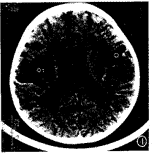

图2 外部性脑积水:额顶区蛛网膜下 腔对称性增宽,宽度达10mm,额顶区大脑沟增宽加深,大脑半球间裂前部增宽,侧脑室扩大 。

3个月内复查CT 30例,CT表现异常19例,其中2个月内复查CT时,12例侧脑室后角或前、后 角周围白质内仍可见斑片状低密度灶。外部性脑积水(EH)1例,CT表现为:额顶区蛛网膜下 腔对称性增宽,宽度≥5mm,大脑半球间裂前部增宽,额顶区大脑沟增宽加深,脑基底池主 要是鞍上池增大,脑室不大或轻度扩大[5,6](图2)。脑室周围白质软化症(PVL)3 例,其中脑软化和脑萎缩1例,结合文献[7],PVL可分为轻、中、重3度,CT诊断 标准为:侧脑室周围白质明显对称性减少或消失,外侧裂池部位脑沟加深,脑灰质逼近侧脑 室缘,与侧脑室缘的距离甚小或消失,侧脑室不同程度扩大,以后角、三角区明显,侧脑 室缘不规整(图3),侧脑室后角或前、后角周围白质内可见斑片状低密度灶。脑积水2例,脑 软化1例。